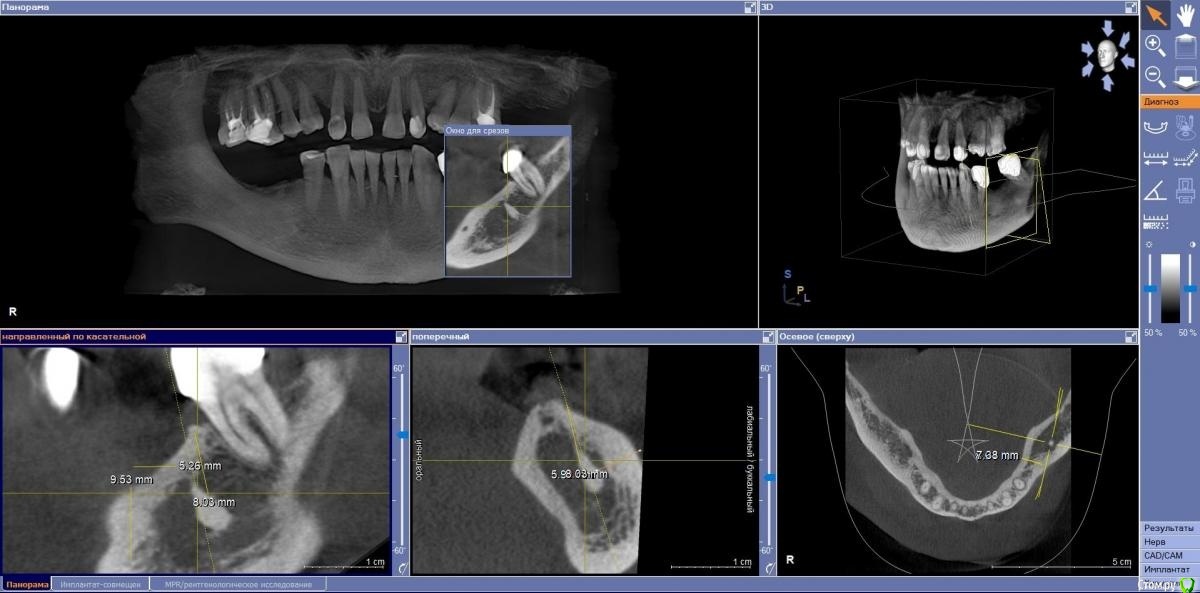

Женька Опубликовано 3 ноября, 2020 Автор Поделиться Опубликовано 3 ноября, 2020 Не скажу что у меня много с этим опыта. Но если мешает для установки импланта, то удалять. Если пациент долго ходит (у меня такой сейчас уже 20 лет с примерно так же похороненным корнем) и имплантация не планируется я бы предупредил пациента и ненастойчиво предложил удалить)) Сделайте скрин среза с размерами до корня, просто непонятно как он глубоко сидит и что вокруг него.Вот такие... но тут как то и не похоже на апекс?Имплантации мешает, но даже если пройтись сверлами и надеяться на полное разрушение этого дела, останутся поднутрения, которые проконтролировать на предмет выскабливания будет сложно... Ссылка на комментарий

Женька Опубликовано 4 ноября, 2020 Автор Поделиться Опубликовано 4 ноября, 2020 Ничего похожего не нашел... только в области 4.7 похоже остит. Обратилась данная пациентка конечно с проблемой разрушенного клыка и желанием имплантации.Я предупредил, что по хорошему бы жевательный отдел сначала восстановить. Потому вот такой план обдумываю:Удаление 4.8Удаление 1.3 и скорее всего контурная пластика. Синус в области 1.6.Имплантация 3.6-3.7. Но обнаружил непонятное и плюсом дента-альвеолярное удлинение в области 2.6-2.7.Как их задвинуть можно? Ссылка на комментарий

Fin Опубликовано 4 ноября, 2020 Поделиться Опубликовано 4 ноября, 2020 Ничего похожего не нашел... только в области 4.7 похоже остит. Обратилась данная пациентка конечно с проблемой разрушенного клыка и желанием имплантации.Я предупредил, что по хорошему бы жевательный отдел сначала восстановить. Потому вот такой план обдумываю:Удаление 4.8Удаление 1.3 и скорее всего контурная пластика. Синус в области 1.6.Имплантация 3.6-3.7. Но обнаружил непонятное и плюсом дента-альвеолярное удлинение в области 2.6-2.7.Как их задвинуть можно?[/size] По мне это все таки не корень , капсулы вокруг образования тоже не вижу, на уплотнение кости не похоже. Я бы сделал прицелку(что бы качество получше было и если не ней все ок то ставил бы, конечно обговорив все моменты с пациентом)А так может кто еще подскажет что за образование.Задвинуть можно мини имплантами, винтами или ортодонтич. пластинкой, но у Вас 16 требует коронки, так что можно и ей. С 17 надо смотреть в полости рта по снимку с кариесом, мб пломбу поставить и покороче сделать, вроде не сильно выдвинут. Ссылка на комментарий